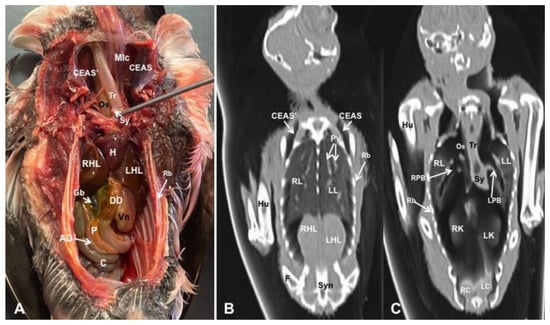

3. Results

3.1. Anatomical Dissections and Cross-Sections

3.2. Computed Tomography Images